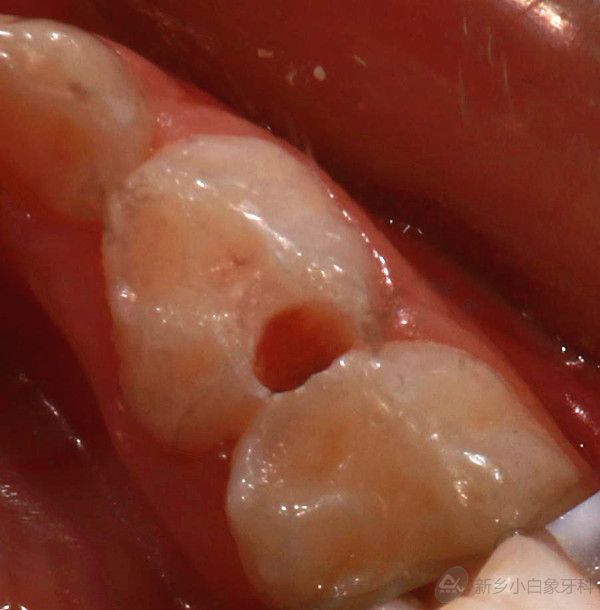

2.jpg

治疗中